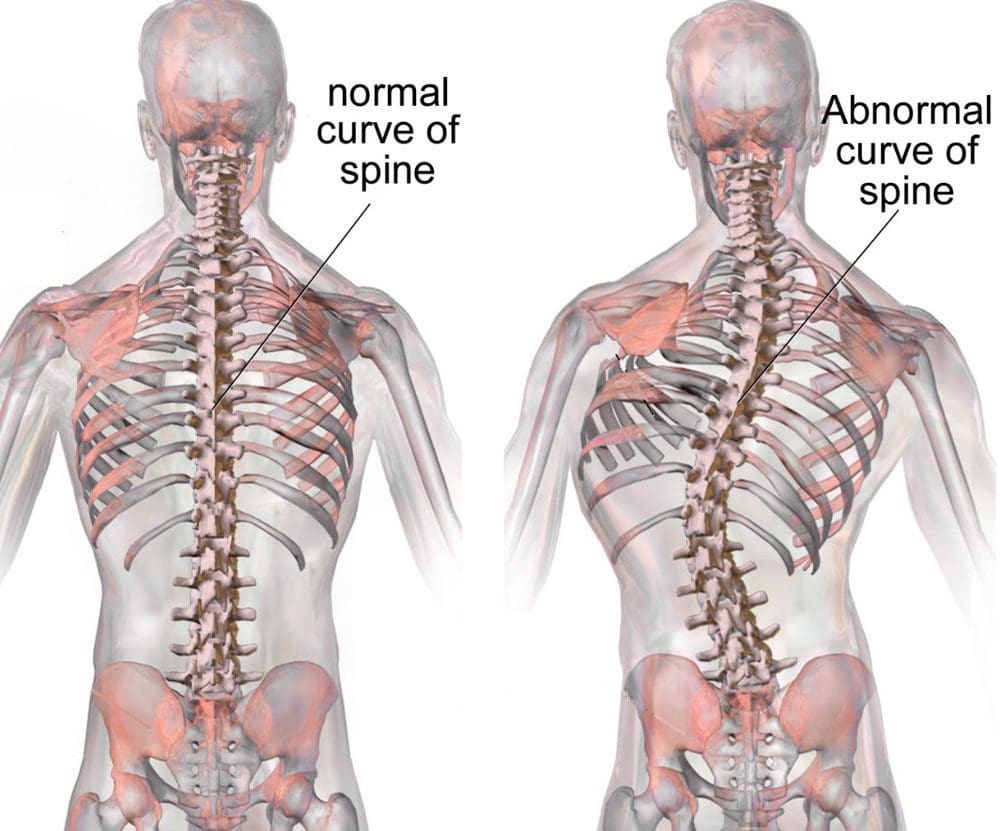

L-ispina hija l-istruttura ewlenija, li żżomm il-qagħda u tagħti lok għal diversi problemi bil-proċessi tal-mard. L-ispina hija magħmula minn seba 'vertebri ċervikali, tnax-il vertebra toraċika, ħames vertebri lumbari, u vertebri sagrali u koġgeġiċi mdewba. L-istabbiltà tas-sinsla tinżamm bi tliet kolonni.

Il-kolonna ta 'quddiem hija ffurmata minn ligament lonġitudinali ta' quddiem u l-parti ta 'quddiem tal-ġisem vertebrali. Il-kolonna tan-nofs hija ffurmata mill-parti ta 'wara tal-ġisem vertebrali u l-ligament lonġitudinali ta' wara. Il-kolonna ta ’wara tikkonsisti f’arkata tal-ġisem ta’ wara li għandha proċessi trasversali, laminati, aspetti, u proċessi spinużi. ("Marda tad-Diska Deġenerattiva: Sfond, Anatomija, Patofiżjoloġija")